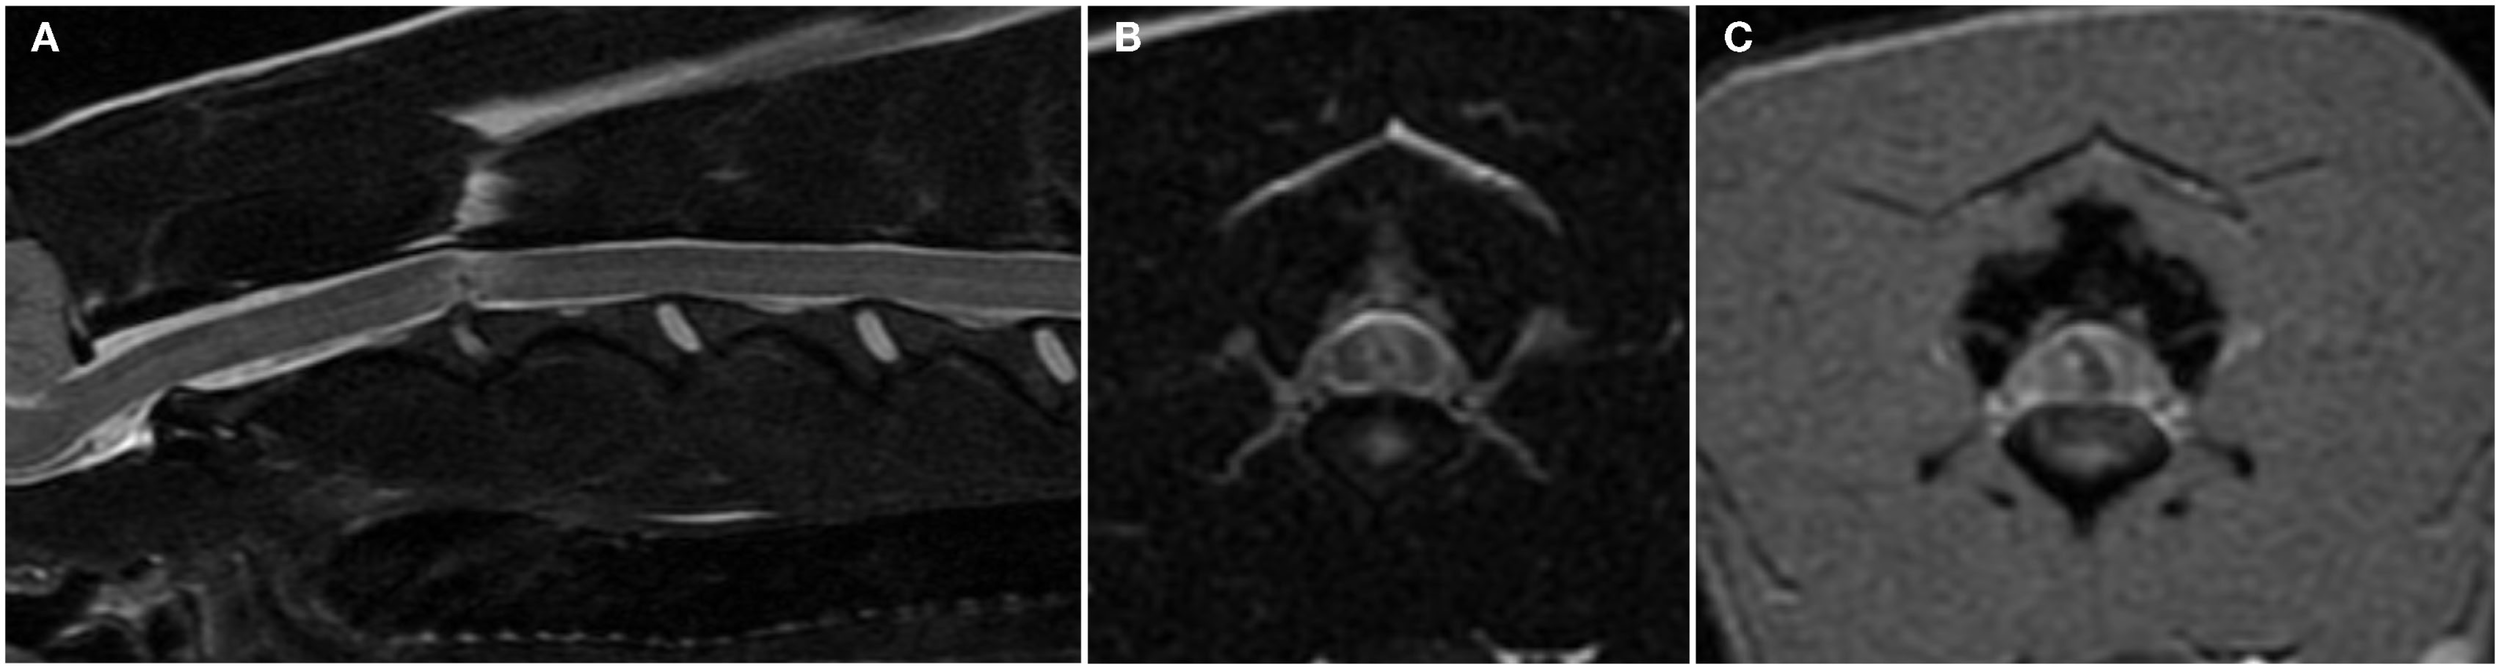

MRI and Computed Tomographic Myelography Findings–IIVDE

In dogs with IIVDE resulting in intramedullary intervertebral disk penetration MRI allows visualization of signal changes within the affected intervertebral disk space and overlying spinal cord parenchyma (28, 29, 36, 46). The intervertebral disk space is generally narrowed and the nucleus pulposus has reduced signal intensity on T2-weighted images. The spinal cord overlying the affected intervertebral disk is swollen. The intramedullary signal changes include an hyperintensity on T2-weighted images and within it, one or more small focal areas of hypointensity on T2-weighted, T1-weighted, and T2*-weighted gradient recall echo images (Figures 3A,B) (28, 29, 36, 46). A linear tract (predominantly hyperintense on T2-weighted images, iso to hypointense on T1-weighted images and hypointense on T2*-weighted gradient recall echo images) extending from the intervertebral disk into the spinal cord parenchyma has been reported in two dogs and two cats undergoing high-field MRI and has been suggested to be specific for intramedullary IVDEs (28, 29, 36, 46). These intramedullary signal changes are most likely consistent with a mixture of extruded intervertebral disk material, edema, malacia, and hemorrhage. The appearance of hemorrhage on MRI is variable and depends upon numerous factors including the time hemorrhage occurred relative to the time of imaging, oxygen tension, size, and location of parenchymal hemorrhage, presence of hematoma, magnetic field strength, and pulse sequence (28, 29). T2*-weighted gradient recall echo images can be particularly helpful in identifying the intramedullary hemorrhage associated with the tract of the intramedullary extruded disk material (Figure 3C) (29, 46). Mild enhancement of the tissue adjacent to the tract can be observed on T1-weighted images following intravenous injection of paramagnetic contrast medium (29, 36, 46).

Figure 3. Sagittal (A) and transverse (B) T2-weighted and transverse T2*-weighted gradient recall echo (C) magnetic resonance images of the cervical spine of a 6-year-old female whippet with peracute onset non-ambulatory tetraparesis after running into a wall. The C2–C3 intervertebral disk space is narrowed and the nucleus pulposus is decreased in size and signal intensity (A). The overlying spinal cord has intramedullary signal changes characterized by a focal hypointensity surrounded by ill-defined hyperintensity on T2-weighted images (A,B) and a curved linear hypointensity on T2*-weighted gradient recall echo images (C). There are no signal changes or extraneous material in the epidural space.